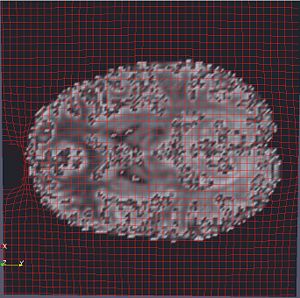

OMT Deformation Grid on MRI

• Preliminary results with DWI baseline image correction.

• DWI and MRI image intensity normalization using CSF and White-Matter/Grey-Matter segmentations performed to make sure both image volumes are on same footing so that Mass Transport mapping is found without introducing structural distortions.